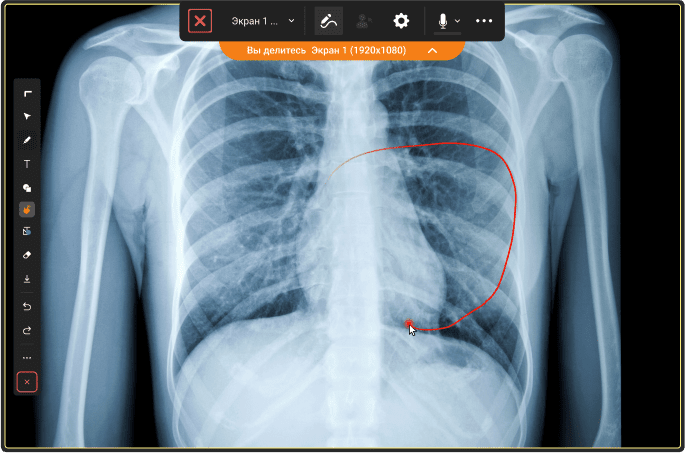

Специалисты «Смарт Дельта Системс» разработали «Инфоклиника.РУ» — цифровой сервис для управления рабочими процессами клиник, а также проведения удаленных медицинских консультаций по видеоконференцсвязи Труконф. Пользователи сервиса записываются на прием к врачам различного профиля удаленно и проходят медицинский осмотр по видеосвязи прямо со своих смартфонов.

В основе сервиса находится защищенная программная ВКС-платформа TrueConf Server, развернутая на серверном оборудовании компании «Смарт Дельта Системс». Это позволяет «Смарт Дельта Системс» полностью контролировать полученную сеть видеосвязи, чтобы сохранить конфиденциальность во время онлайн-консультаций и защитить данные пациентов клиник от доступа третьих лиц.